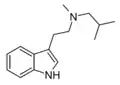

| MiPT | artificial | H | CH3 | CH(CH3)2 | N-Methyl-N-isopropyltryptamine | 96096-52-5 |

| MiBT | artificial | H | CH3 | CH2CH(CH3)2 | N-Methyl-N-iso-butyltryptamine | |